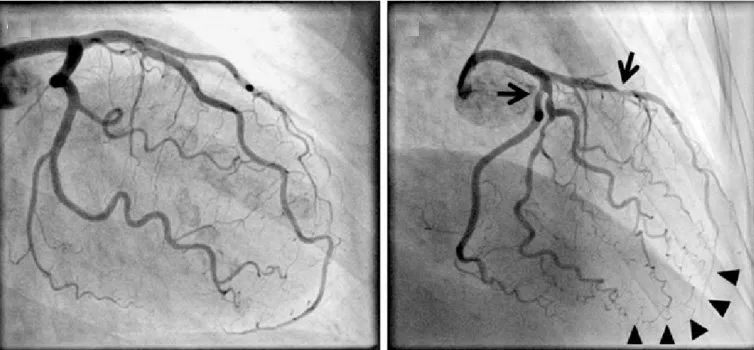

• Mảng xơ vữa không ổn định: Loại mảng bám này có sự tăng trưởng không liên tục và không đều, bao gồm một lõi lớn chứa nhiều chất béo giàu cholesterol (LDL), lẫn với các tế bào miễn dịch và các yếu tố mô. Lõi này được bao bọc bởi một lớp sợi mỏng (50-65 mcm) có dấu hiệu xói mòn và sẹo. Khi chụp động mạch, mảng bám này có thể chỉ biểu hiện bằng hẹp trung bình (≤ 50%) và không hạn chế dòng chảy phía hạ lưu, vì nó có xu hướng phình ra ngoài và không đi vào trong lòng động mạch. Nguy cơ của mảng bám này phụ thuộc vào hoạt động viêm và tính nhạy cảm của nó đối với sự vỡ, chứ không phụ thuộc vào mức độ hẹp mà nó gây ra. Mảng xơ vữa không ổn định có thể được phát hiện bằng phương pháp chụp động mạch vành. Loại mảng bám này ít gây hẹp nặng (<60%), do đó không ảnh hưởng nhiều đến việc cung cấp oxy (DO2). Đau thắt ngực thường hiếm gặp, và chụp động mạch có thể cho thấy hẹp không đáng kể, thậm chí test gắng sức cũng có thể âm tính. Tuy nhiên, mảng bám này có thể bị mất ổn định, vỡ ra và gây huyết khối trong động mạch, dẫn đến thiếu máu cục bộ. Điều này có thể dẫn đến nhồi máu với sóng Q và ST chênh lên (STEMI). Mảng bám không ổn định chịu trách nhiệm cho 40-50% các trường hợp nhồi máu sau phẫu thuật (thường xảy ra trong vòng 36 giờ sau phẫu thuật). Điều trị dự phòng tập trung vào việc sử dụng thuốc chống tiểu cầu và statin để ổn định mảng bám và ngăn ngừa huyết khối [tham khảo: AHA Journals].